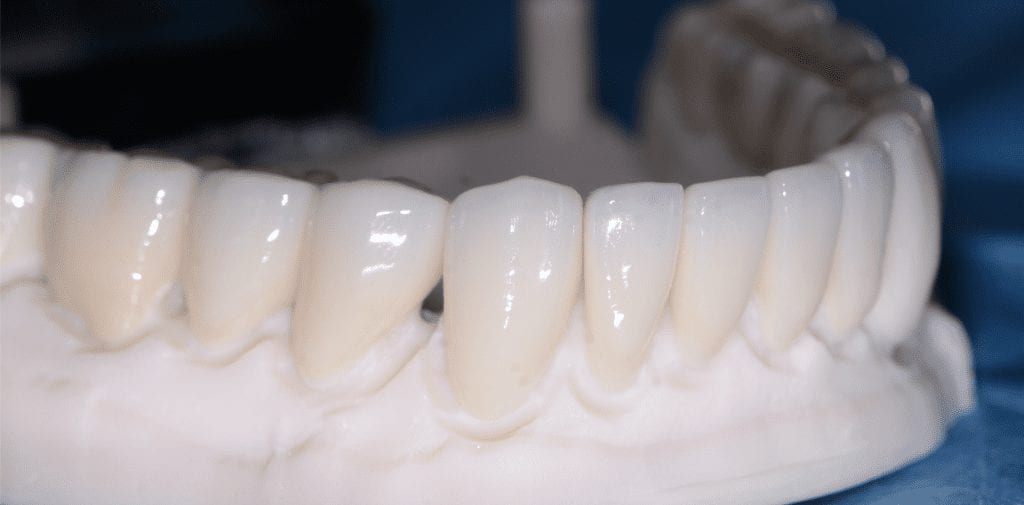

The case was designed by CADENT BESSA, and the models were printed by Burbank Dental Lab with Carbon Printers. There restorations were milled and cut back and layered by Burbank Dental Lab

IMAGES OF PRINTED MODELS